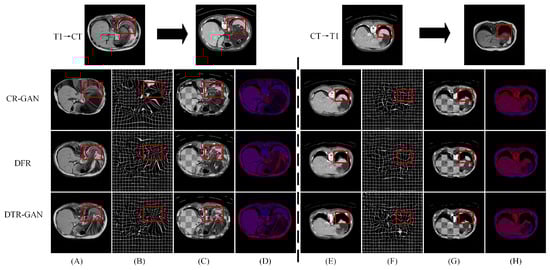

Figure 5 shows the registration results of some methods on the Learn2Reg dataset. Figure 5A,E show warped images, Figure 5B,F show deformation fields, and Figure 5C,D,G,H show checkerboard grids and overlapping images, respectively, which are visualizations of image alignment effects. Figure 5A,E show the warped images in DTR-GAN are closer to the target image. The first in column (A) denotes that the cycle-consistency loss would lead to shape distortion in CR-GAN. We can observe that DTR-GAN with similarity loss is more effective for appearance preservation in image registration. Figure 5D,H show the effects of overlaying the target image with the warped image, in which the target image is set to blue, the warped image is set to red, and the two images are superimposed together in purple. The purple in the image is more evident, indicating that the warped image and target image are better aligned. As shown in Figure 5, DTR-GAN shows an optimum performance.

Figure 5.

Experimental results on the Learn2Reg dataset: (A,E) are warped images, (B,F) are deformation fields, (C,G) are checkboard grids, and (D,H) are overlapping images.